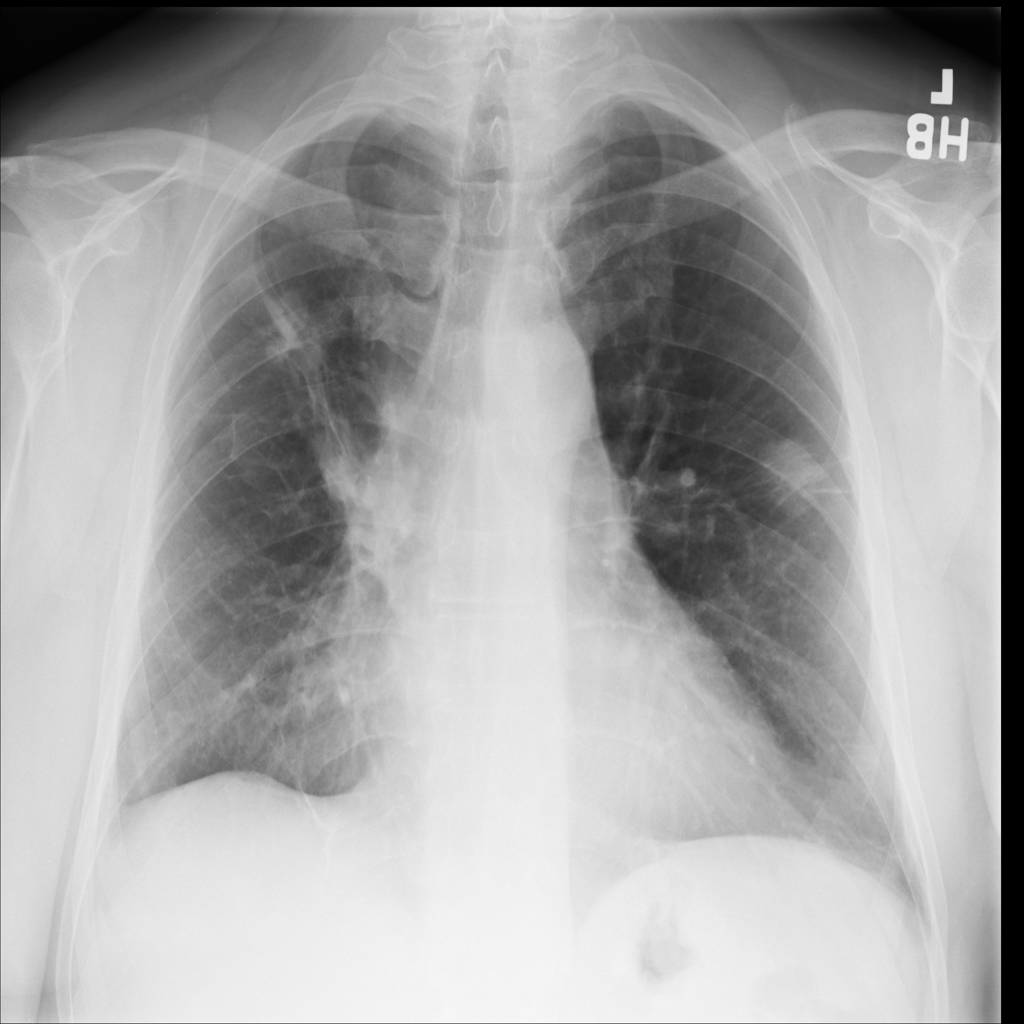

Mass

A mass is a larger focal opacity or lesion seen on the image. It is a descriptive finding that can have several causes and usually needs more imaging or clinical context to characterize.

PAT-D7A5 · IMG-000Mass

PAT-D7A5 · IMG-000

PA